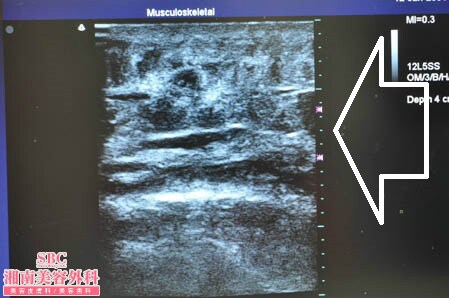

No.160662【脂肪吸引】圧倒的吸引量で圧倒的満足度!あの有名な根こそぎ竹田先生の劇的ビフォーアフター!〜東北地方からご来院された現役ナースさんの二の腕を細くする!右二の腕術中3Dタッチビュー〜

ではいつものように右の二の腕の

3Dタッチビューの画像から。

白い矢印部分が皮下脂肪層ですが

しっかりと薄くなっていますね。